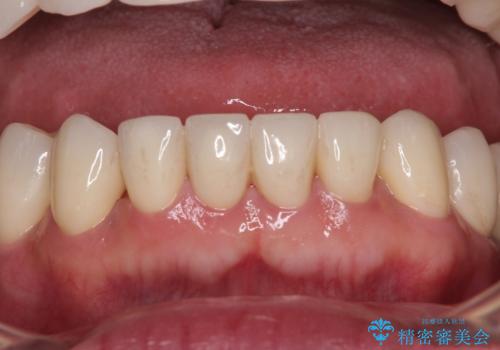

欠損部はインプラントによる補綴治療を行うこととし、臼歯部が安定した後に、上下前歯部をオールセラミッククラウンにて補綴治療を行うこととしました。

上顎前歯に歯周ポケットの深い部分がありましたが、インプラントの仮歯で奥歯がしっかりと噛めるようになると、1年程度で深い歯周ポケットは解消されました。

前歯部の審美面も大幅に改善され、大変満足していただけました。